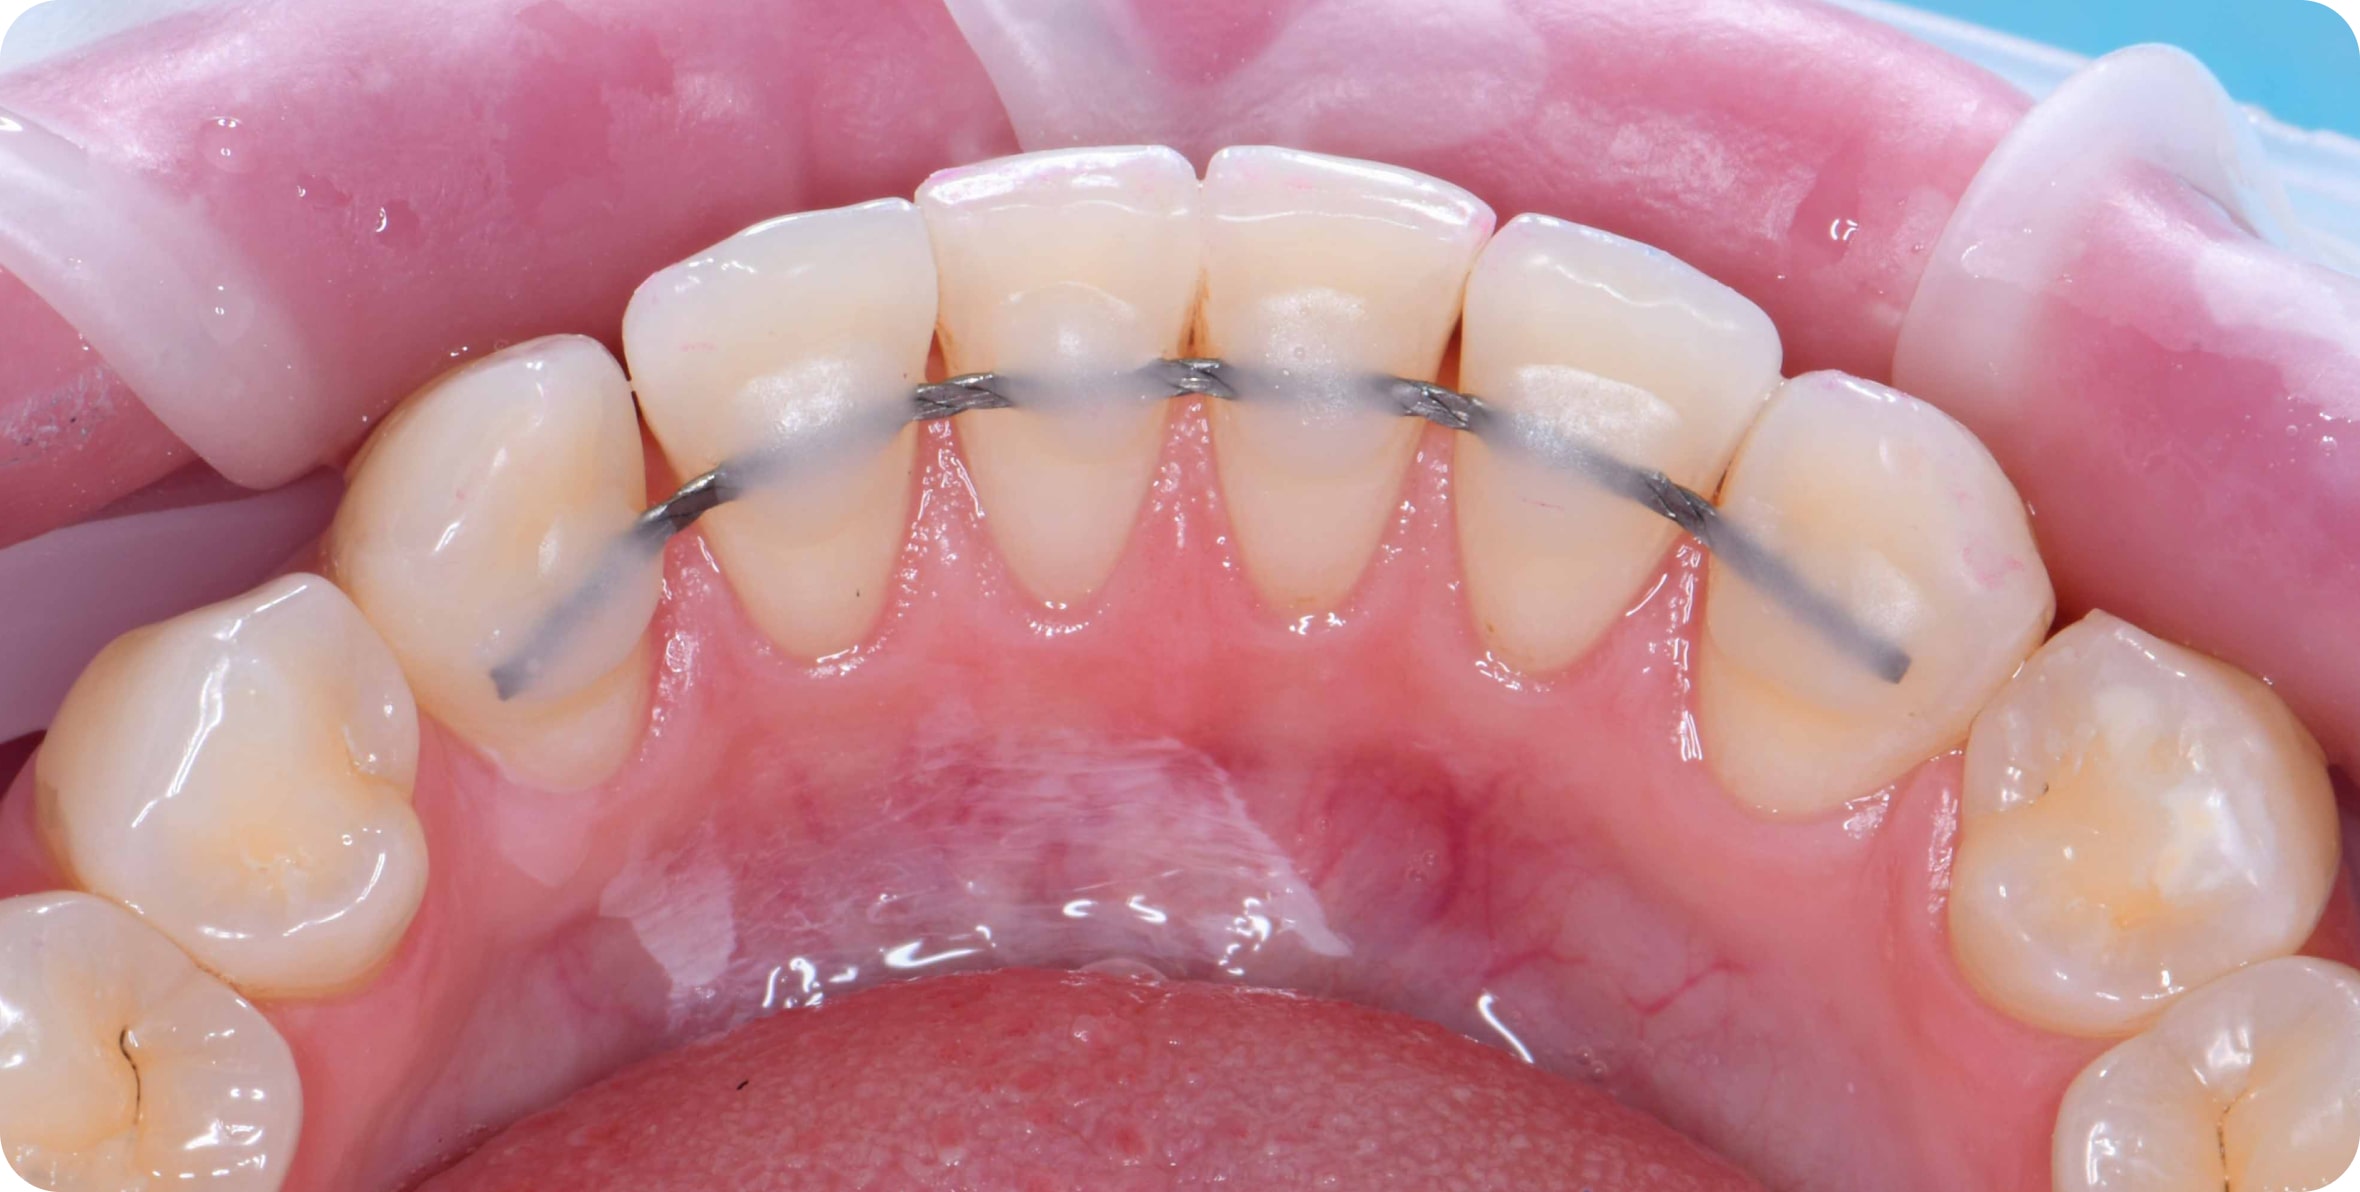

Что такое ретейнер?

Ретейнер - металлическая проволока, которая устанавливается на задней поверхности зубов для сохранения результата

Мы всегда устанавливаем ретейнеры, и это уже входит в стоимость лечения

Ретейнеры устанавливают на 5-10 лет

Что такое ретейнер